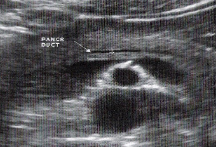

Neck/Body- SV, SMA, AO, Wirsung’s duct